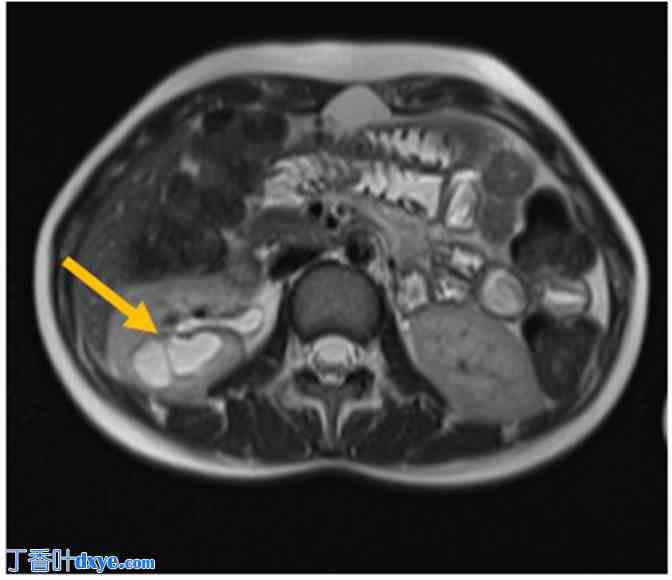

图 3.

注射造影剂后的横断面 MRU 图像显示双叶囊性病变已完全充盈(箭头)。